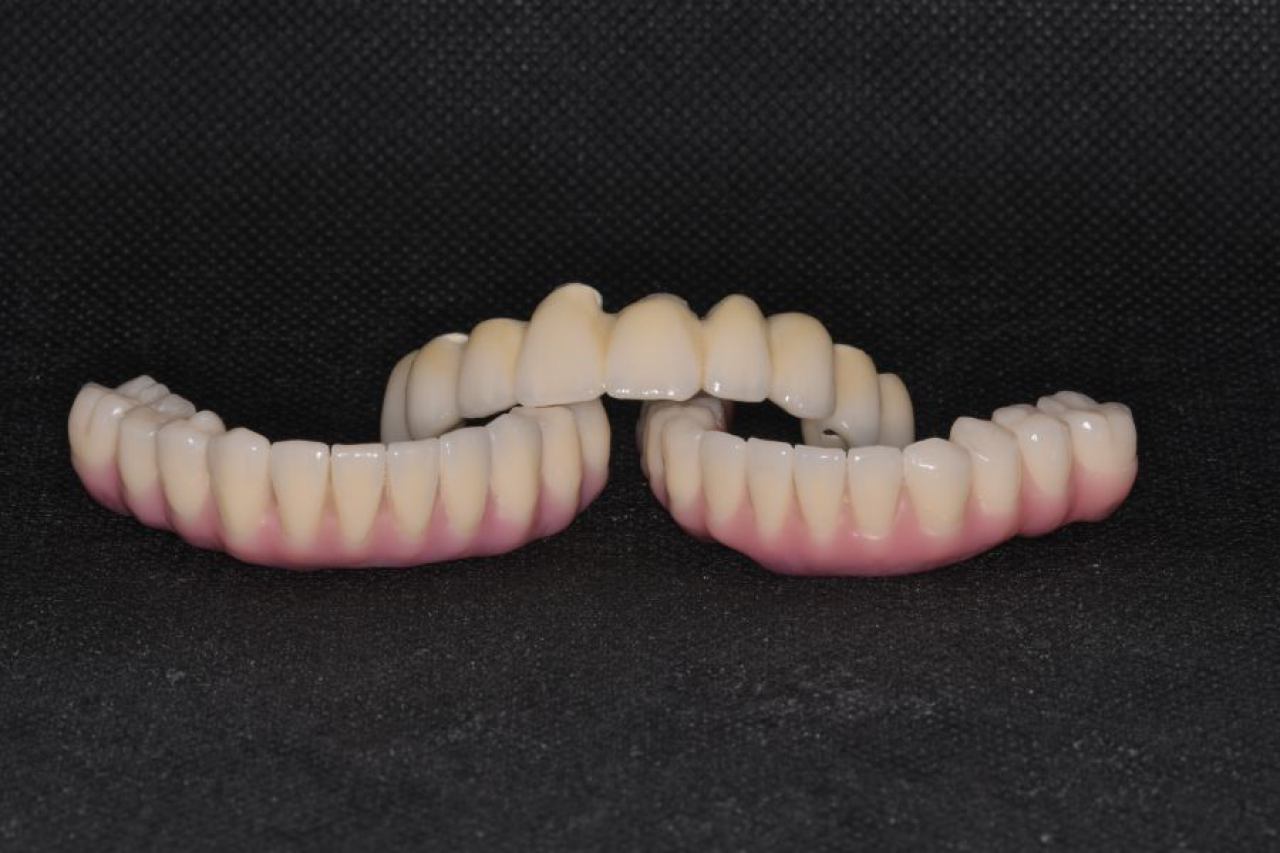

Protetika - mostovi i krunice

Dentalna protetika uključuje fiksne i mobilne radove kojima se nadoknađuje djelomična ili potpuna bezubost. Njihov cilj je povratiti funkciju žvačnog sustava i u konačnici, vrhunsku estetiku.

Marković Dental Clinic u svojoj ponudi ima metalkeramičke radove, potpunokeramičke radove, te u narodu zvane „bezmetalne", odnosno zirkonske radove.